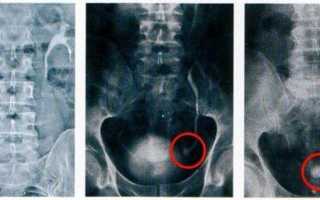

Мочекаменной болезни подвержены люди любого возраста и пола. Диагностируется при помощи медицинских клинических анализов и общих жалоб пациента. Для заболевания характерно образование камней в мочевыделительной системе. Они могут быть разными по величине и диаметру, чаще всего встречается песок. Бывают и образования размерами от 0,5 см до 5—6 см.

Редкие виды конкрементов

Помимо описанных выше камней в почках могут присутствовать и другие образования – цистиновые, белковые, холестериновые и прочие конкременты. Как вы понимаете, они также отличаются составом и некоторыми особенностями.

Так, струвиты представляют собой коралловидные конкременты, включающие в состав магний, карбонат кальция и фосфат аммония. Они быстро растут, окрашены в белый цвет, который может иметь желтоватый оттенок.

Очень редко в организме образуются холестериновые конкременты. Они черные, мягкие и легко крошащиеся. Мягкой консистенцией обладают и округлые цистиновые камни, окрашенные в желтовато-белые цвета, отличающиеся гладкостью поверхности. На фоне генетического дефекта, под воздействием которого образуется дефицит ксантиноксидазы, формируются ксантиновые конкременты.

Белковые камни обычно формируются из фибрина, к которому примешиваются соли с бактериями. Их отличают небольшие размеры, мягкая консистенция, плоская форма. Цвет таких конкрементов – белый. В образовании карбонатных камней принимают участие кальциевые соли угольной кислоты. Такие конкременты окрашены в белый цвет, имеют гладкую поверхность, демонстрируют разнообразные формы и мягкую консистенцию.